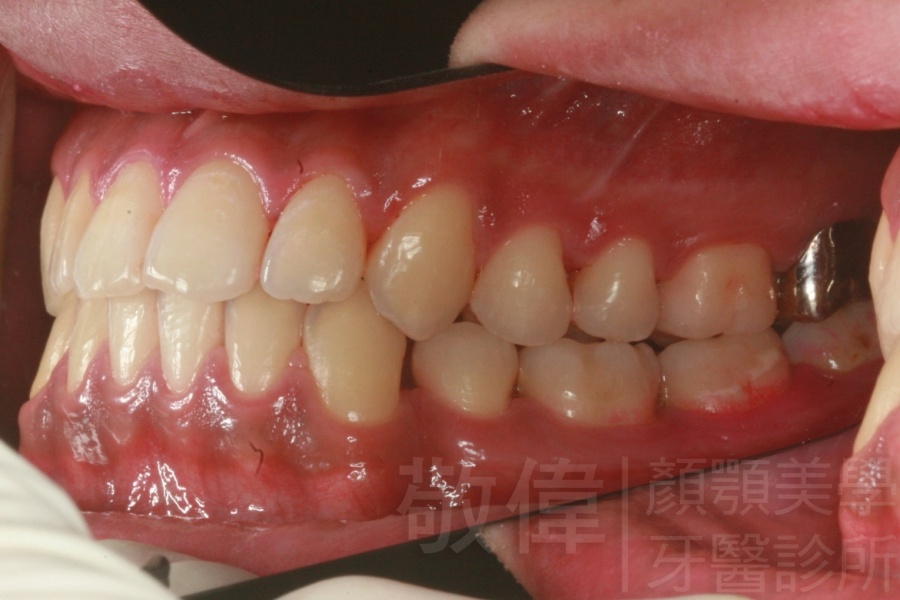

矯正前-右   矯正前-正   矯正前-左

矯正後-右   矯正後-正   矯正後-左

<個案說明>

上下暴牙嘴唇不容易合起來,經矯正完成後,嘴唇很容易合起來。在學生時期的時候的他,舉止之間充滿著有自信,當時還參加了舞蹈社團,充滿了多采多姿的生活。